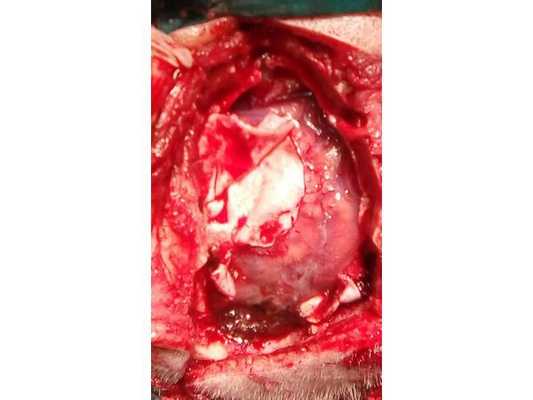

Субдуральная гематома удалена. В нижнем углу оперативного доступа визуализирована сосудистая мальформация

Пациент взят на операцию: ⠀•⠀Выполнен дугообразный разрез мягких тканей в правой лобно-височно-теменной области. Скелетирована кость. ⠀•⠀Наложены два фрезевых отверстия, из которых краниотомом выпилен костный лоскут 6,0*8,0 см. ⠀•⠀Произведён гемостаз моно- и биполярной коагуляцией, воском по ходу доступа. ⠀•⠀Твёрдая мозговая оболочка вскрыта подковообразно. Визуализирована субдуральная гематома, представленная плотными сгустками тёмно-вишнёвого цвета (рис. 3). ⠀•⠀Начато удаление сгустков путём аспирации и отмыванием физиологическим раствором. Общий объём субдуральной гематомы около 120 мл. Признаков черепно-мозговой травмы (кортикальных очагов ушиба, травматического субарахноидального кровоизлияния, гиперемии, отёка головного мозга) нет. ⠀•⠀При удалении сгустков с конвекситальной поверхности лобной доли открылось интенсивное венозное кровотечение. С целью доступа к источнику кровотечения разрез мягких тканей продолжен в конвекситальном направлении и краниотомом выпилены два дополнительных костных лоскута (из-за интенсивности кровотечения найти локализацию источника было затруднительно). ⠀•⠀Визуализировано кровоточащее образование, сращённое с твёрдой мозговой оболочкой и корой головного мозга, по виду — сосудистая мальформация (рис. 4). ⠀•⠀Гемостаз подходящих сосудов и самого образования выполнен последовательной биполярной коагуляцией (рис. 5: сосудистая мальформация указана наконечником аспиратора). ⠀•⠀Кровотечение остановлено. Мозг расправился, пульсирует. Твёрдая мозговая оболочка ушита викрилом с одновременным подшиванием по периметру трепанационного окна (рис. 6). ⠀•⠀Дефекты твёрдой мозговой оболочки и сосудистая мальформация укрыты гемостатической губкой (рис. 7). ⠀•⠀Костные лоскуты уложены на место (рис. 8). ⠀•⠀Послойный шов раны выполнен викрилом и капроном. ⠀•⠀Кожа ушита обвивным швом по Мультановскому. Ретроспективно на фронтальной ангиограмме можно заподозрить сосудистую мальформацию, ставшую источником гематомы (рис. 9). На девятые сутки после операции для обеспечения проходимости дыхательных путей, проведения длительной искусственной вентиляции лёгких, облегчения санации трахеи и бронхов пациенту выполнена нижняя трахеостомия по Бьёрку.